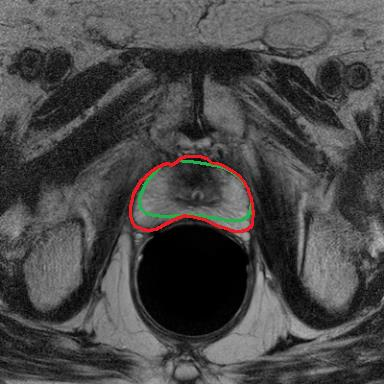

Modern deep neural networks struggle to transfer knowledge and generalize across diverse domains when deployed to real-world applications. Currently, domain generalization (DG) is introduced to learn a universal representation from multiple domains to improve the network generalization ability on unseen domains. However, previous DG methods only focus on the data-level consistency scheme without considering the synergistic regularization among different consistency schemes. In this paper, we present a novel Hierarchical Consistency framework for Domain Generalization (HCDG) by integrating Extrinsic Consistency and Intrinsic Consistency synergistically. Particularly, for the Extrinsic Consistency, we leverage the knowledge across multiple source domains to enforce data-level consistency. To better enhance such consistency, we design a novel Amplitude Gaussian-mixing strategy into Fourier-based data augmentation called DomainUp. For the Intrinsic Consistency, we perform task-level consistency for the same instance under the dual-task scenario. We evaluate the proposed HCDG framework on two medical image segmentation tasks, i.e., optic cup/disc segmentation on fundus images and prostate MRI segmentation. Extensive experimental results manifest the effectiveness and versatility of our HCDG framework.